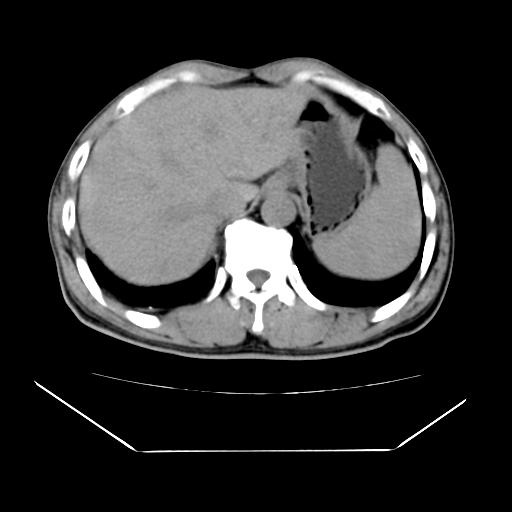

男性,55岁,外院体检afp明显升高,但b超未发现异常,否认乙肝病史。来我院ct增强。有延时扫描。

延时扫描完全充填,血管瘤

肝脏右叶动脉期可见低密度影,至延迟期被充填,考虑血管瘤可能性大。

肝右叶病灶

不排除肝右叶肝癌可能。

这个不是肝右静脉吗,这么大的病灶b超不可能发现不了吧

如果这个是癌灶的话则下腔静脉有瘤栓可能

肝6段血管瘤

血管瘤可能性大。

是肝右静脉吧

考虑肝右静脉影。